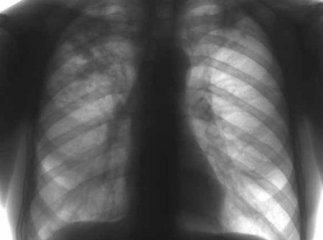

За даними статистики, туберкульоз в Україні є найпоширенішою інфекційною хворобою, яка займає перше місце в структурі смертності людей від інфекційних захворювань. Не секрет, що ця хвороба руйнує не тільки здоров’я людей, а й їхні долі.

Окрім того, обоє батьків тривалий час хворіли на інфекційне захворювання – туберкульоз. Як пояснює жінка, спочатку вони надавали своїй хворобі велике значення – лікувались в тубдиспансері, пізніше вдома. Та не дочекавшись результату – вирішили далі не продовжувати. Так, наразі і в Ольги, і в її чоловіка медики констатували відкриту бацилярну форму туберкульозу, що загрожує життю і здоров’ю їхніх дітей.